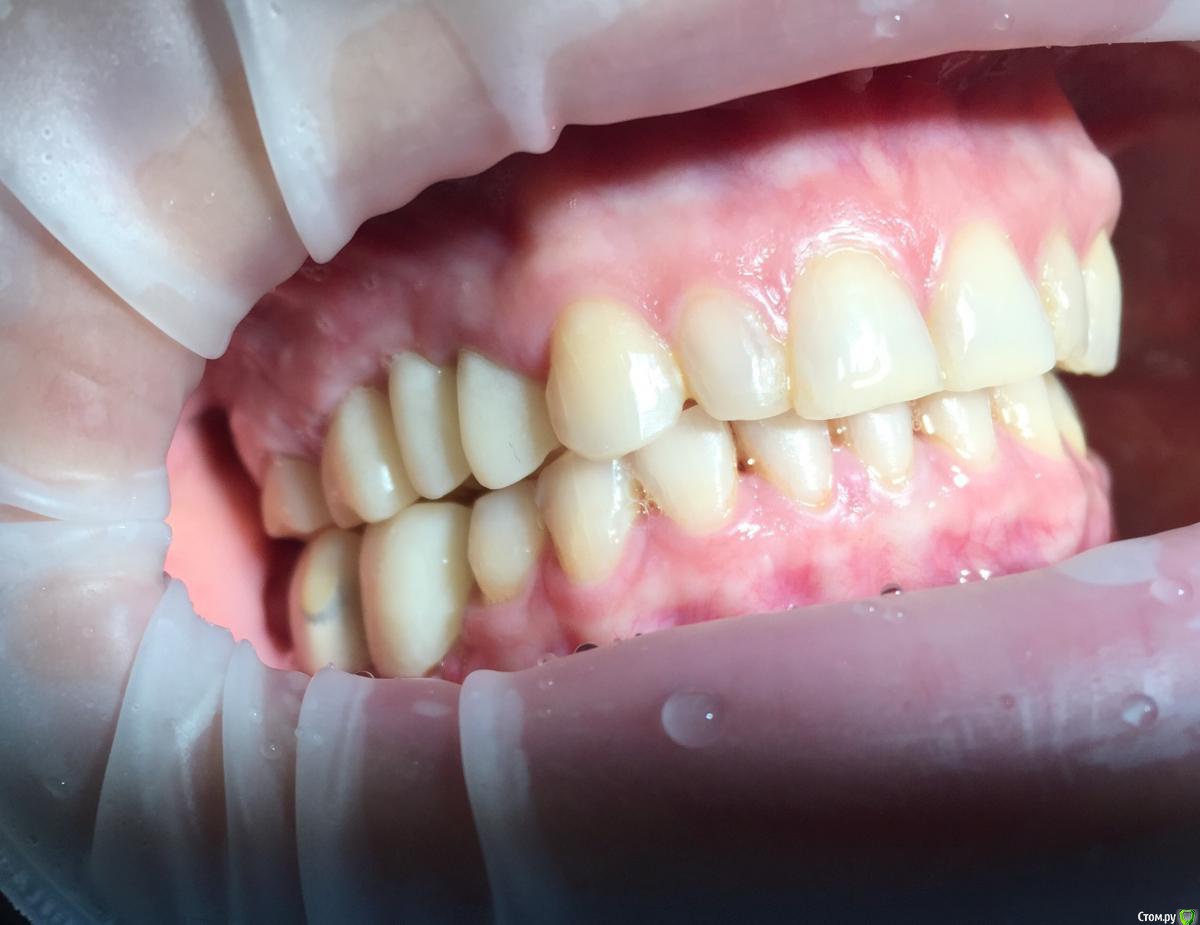

Глеб Митрофанов Опубликовано 12 сентября, 2015 Поделиться Опубликовано 12 сентября, 2015 (изменено) Направлена ортопедом , к которому пришла от другого хирурга и ортопеда , которые оперировали и изготавливали времянки соответственно . Пришла с просьбой - хочу сосочки ! Изменено 12 сентября, 2015 пользователем Глеб Митрофанов Ссылка на комментарий

Глеб Митрофанов Опубликовано 12 сентября, 2015 Автор Поделиться Опубликовано 12 сентября, 2015 А какой вопрос? С какой целью написали?Что возможно сделать , чтоб сделать максимально приближенное к желаемому ? Работа с мягкими тканями , времянками ?? Ссылка на комментарий

faity Опубликовано 12 сентября, 2015 Поделиться Опубликовано 12 сентября, 2015 пластика с бугров наверху, снизу полностью переделывать ортопедию и делать пластику с бугров. Гамборена вчера показывал как))) carlos показывает уже год 4 Ссылка на комментарий

Aquarius Опубликовано 12 сентября, 2015 Поделиться Опубликовано 12 сентября, 2015 Что возможно сделать , чтоб сделать максимально приближенное к желаемому ? Работа с мягкими тканями , времянками ??Если имплант не глушить, то по моему никак Ссылка на комментарий

Mane Опубликовано 12 сентября, 2015 Поделиться Опубликовано 12 сентября, 2015 снимаешь временную коронкупересаживаешь сст с бугра на тонкий формировательждешь месяцоцениваешьпротезируешь 2 Ссылка на комментарий